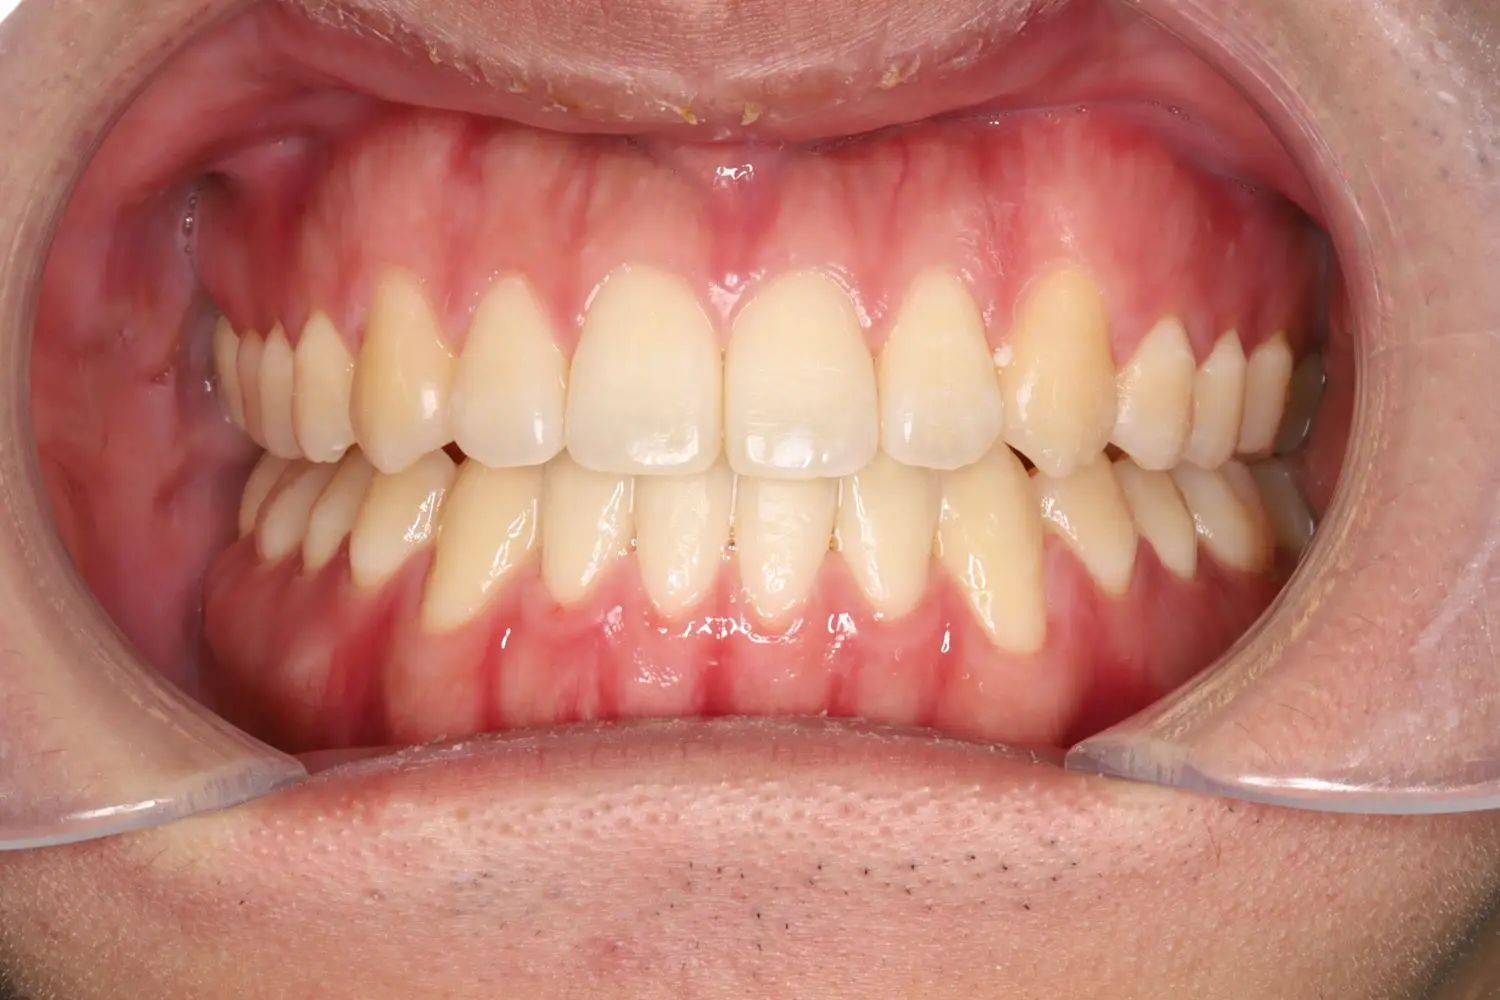

| 年齢 | 20代男性 |

| 主訴 | 前歯でモノが噛めない |

| 治療期間・治療回数 | 1年3か月 |

上顎歯列と下顎歯列の咬合平面を一致させることで非抜歯にて開咬を改善することができました。患者様の協力度が高く、ゴムかけを頑張ってくれたので短期間で動的治療を終了できました。